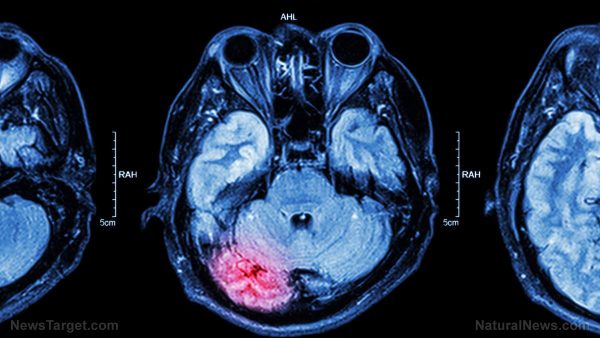

Accident victims who suffer a traumatic brain injury usually undergo prophylactic hypothermia ("brain cooling") in order to protect the fragile organ from further harm. However, a new Australian-led study has concluded that this practice does not actually benefit the patient, reports The BMJ news article. Cooling the brain was previously believed to decrease the harmful inflammation and biochemical cascades caused by traumatic brain injury. This would preserve more of the brain functions of the patient over the long term. However, studies conducted to determine the actual effectiveness of brain cooling contradicted each other. Some claimed it was effective at improving neurological outcomes while others reported a disappointing lack of effect. Researchers from Monash University (Monash) conducted a massive randomized clinical trial that involved more than 500 patients with traumatic brain injuries. They reported that only 48.8 percent of the participants who underwent brain cooling displayed better brain functions six months after treatment. In comparison, patients who had normal temperatures during treatment experienced slightly better results at 49.1 percent. (Related: Delicious remedy: Licorice is a potential treatment for ischemia-induced brain damage.)